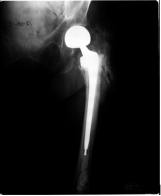

A 67-year-old white female underwent an open reduction and internal fixation (ORIF) due to a comminuted reversed oblique fracture of the left intertrochanteric hip. The ORIF subsequently failed and a conversion to a bipolar hemiarthroplasty was performed. Radiograph of left hip Hemiarthroplasty shows evidence of loosening at the bone cement interface (Figure 1). Increased cortical density is seen in the portion of the femur containing the endoprosthesis. Heterotopic ossification is seen in the proximal femoral region with no extension across the joint. CT scans were performed on the right and left hip. Slices 91-118 had focused on the proximal femur, neck, trochanter and intertrochanteric regions. For comparison slices from both hips were measured. To be congruent with the results same number of slices were measured for both the hips. The Hounsfield units (HU) were obtained using the probe tool. The CT scans had used calibrated images to provide necessary information to define a linear equation which would convert intensity of an image in HU to its apparent density (ρ) in gm/cm3 (equation 1a). For larger HU values, another linear equation was defined (equation 1b) [9].